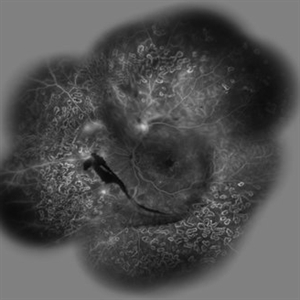

Behcet's Disease Behcet's DiseaseMar 13 2013 by Hamid Ahmadieh, MD Late phase FA of the left eye of a 23-year-old man with retinal vasculitis due to Behcet's disease . Photographer: Solmaz Shahmohammad, Negah Eye Center, Tehran Imaging device: Heidelberg Spectralis Condition/keywords: retinal vasculitis

Behcet's Disease Behcet's DiseaseMar 13 2013 by Hamid Ahmadieh, MD Wide field FA of the left eye of a 23-year-old man with retinal vasculitis due to Behcet's disease . Photographer: Solmaz Shahmohammadi , Negah Eye Center, Tehran Imaging device: Heidelberg Spectralis Condition/keywords: retinal vasculitis